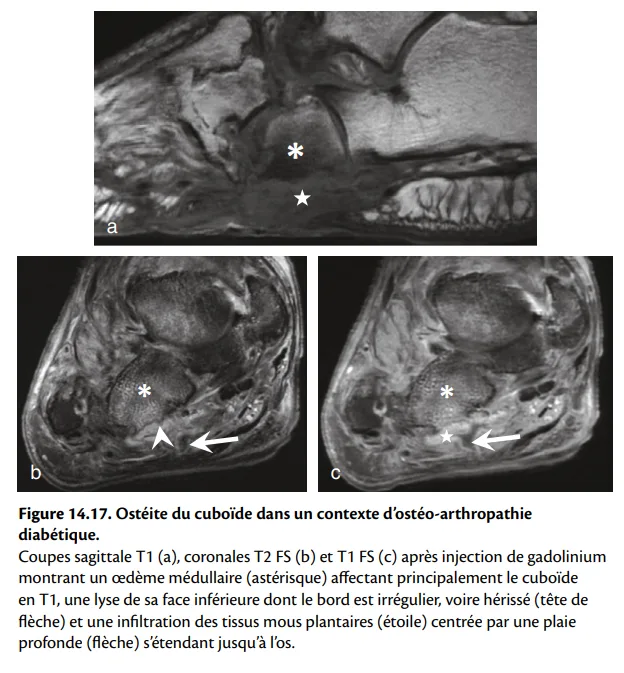

Les arguments en faveur d’une atteinte infectieuse et d’une ostéomyélite sont (figures 14.17 et 14.18) :

la présence d’une plaie (mal perforant plantaire) : pas de plaie, pas d’infection ;

une plaie qui s’étend à l’os : pas de contact osseux, pas d’ostéomyélite ;

l’atteinte d’un seul os (contrairement à l’atteinte multifocale d’un pied de Charcot en phase aiguë) ;

la présence d’une collection (infection des tissus mous) ;

la présence d’une réaction périostée (infection osseuse) ;

un ghost sign marquant une ostéomyélite : os mal visible en pondération T1, dont les contours réapparaissent en T2 ou après injection de gadolinium ;

la disparition des kystes sous-chondraux et de fragments intra-articulaires qui sont l’apanage du pied de Charcot non infecté.